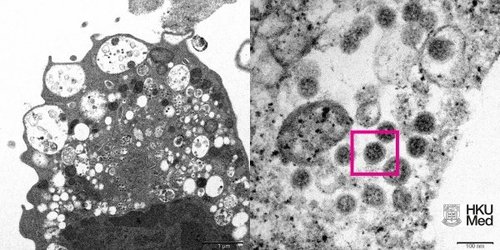

Омикрон штаммын зургийг анх удаа авчээ

Томруулсан зурган дээр гадаргуу дээрээ титэм хэлбэртэй өргөсүүдтэй вирусийн хэсгүүд харагдаж байгаа аж.